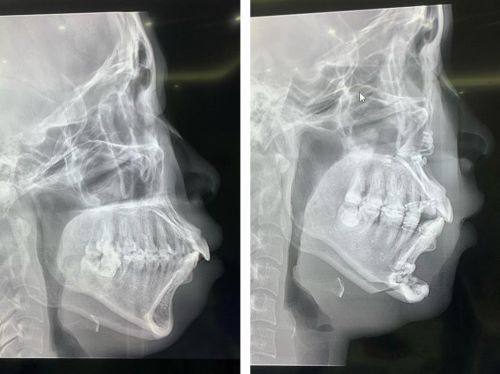

1. 牙齿美容与正畸:梁亚涵医生在牙齿美容和正畸方面有着深厚的造诣。他擅长运用精良的技术和理念,针对不同患者的牙齿情况制定个性化的方案。对于牙齿不齐、牙齿颜色不佳等问题,他能通过正畸治疗和美容修复,让患者拥有整齐洁白的牙齿。例如,对于牙齿不齐嘴巴歪的高龄疑难患者,他也能凭借丰富的经验和不错的技术进行矫正,使矫正取得不错的成效。

1. 患者小李,因牙齿不齐嘴巴歪的问题困扰多年。在朋友的推荐下,他找到了梁亚涵医生。梁医生为他制定了详细的矫正方案,在矫正过程中,梁医生耐心地解答他的每一个疑问,还会根据他的修复情况及时调整方案。经过一段时间的矫正,小李的牙齿变得整齐了,嘴巴歪的问题也得到了明显改善。小李说:“梁医生技术真的特别棒,而且特别有耐心。现在我的牙齿变好看了,整个人也自信了特别多。真的非常感谢梁医生。”

地包牙齿矫正:7233元起

错颌矫治手术:15015元起

下颌手术磨骨头:46270元起